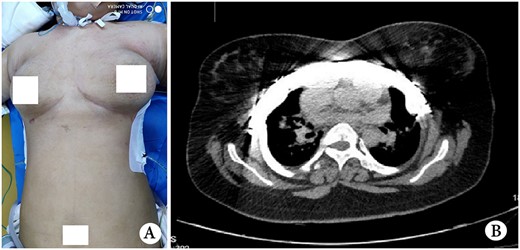

Asphyxiating thoracic dystrophy (ATD) is an autosomal recessive disease first reported by Jeune in 1955 [1, 2]. The disease is extremely rare and fatal. Since most patients die in the first year of life, patients surviving to adolescence are more rarer [1]. ATD has serious impacts on physical development, and most patients are thin and short. However, we received a 16-year-old female ATD patient, whose physical development exceeded the normal level (Fig. 1A). Because her chest was narrow and small, her condition was serious, and operation was the only choice to save her life. We performed surgery for her and achieved satisfactory results.

(A) Thorax appearance before operation; (B) CT scan image before operation; (C) schematic diagram of operation and (D) operation Picture.

The female patient had a full-term natural birth, and was the only child of an unrelated couple. She had dyspnea after birth and was treated with ventilation for one week. ATD was diagnosed at that time. Since then, she suffered from hypoxia for many times and gradually relieved after oxygen administration. Her condition improved after the age of five. Her activities were slightly limited, but physical development was not significantly different from that of children of the same age. At the age of 12, her body began to grow rapidly, and dyspnea gradually appeared. Her symptoms worsened a year before admission. Finally, at the age of 16, she was admitted to our hospital for surgery. Physical examination showed that her height was 167 cm, and weight 71 Kg; her thorax was narrow and small, and the ratio of thorax to trunk was uncoordinated (Fig. 1A). Computed tomography scan showed that the thorax was narrow, the lateral chest walls were sunken, and both lungs were compressed obviously (Fig. 1B). The operation was performed on both sides of the chest walls simultaneously. We used Wenlin procedure [3] and Wang procedure [4] to perform the operation. A longitudinal incision was made at the axillary midline to expose all ribs and costal cartilages. Two arc-shaped steel bars were inserted through the front of the sternum, with both sides of the bar located in front of the concave part of chest wall. The main concave parts were lifted and fixed on the steel bars with steel wires, and the other small concave parts were lifted and fixed on two additional short steel bars (Fig. 1C and D). After the concave parts were eliminated, the incisions were closed, and the operation was completed (Fig. 2A). Ventilator was used continuously for 1 week after operation. After the condition was stable, she weaned and changed to nasal catheter for oxygen. The oxygen saturation was maintained above 91%. Her chest circumference increased from 71 to 81 cm, and examination showed her thorax improved significantly after operation (Fig. 2B). She was discharged 25 days after operation, and recovered satisfactorily without symptoms. The bars were removed 2 years later, and there was no recurrence postoperatively.